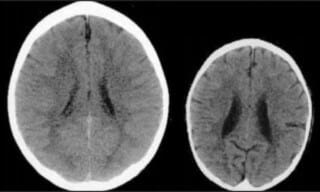

De afbeelding hieronder is een beeld van de hersenen van twee kinderen: de linker groeide op met een aandachtige verzorger die hem continu liefde gaf, voor hem zorgde, reageerde op zijn vragen en positieve interacties met hem had. Het kind aan de rechterkant werd genegeerd, verwaarloosd en mishandeld.

“Het kind aan de rechterkant zal zich ontwikkelen tot een volwassenen met lagere intelligentie, verminderd vermogen tot empathie voor anderen, heeft een verhoogd risico om verslaafd te raken aan drugs en in aanraking te komen met gewelddadige misdaad … en om mentale en andere serieuze gezondheidsproblemen te ontwikkelen,” zo stelt een artikel van de Britse krant The Telegraph.